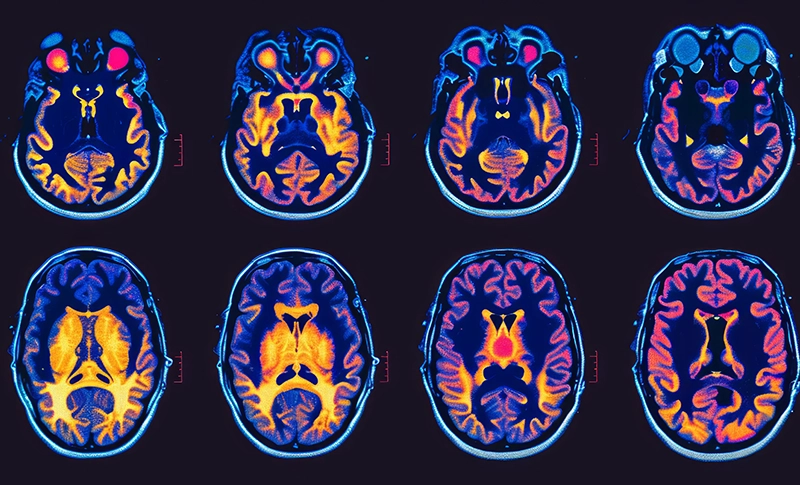

Brain Cancer

Molecular profiling is a critical step in the diagnosis and treatment of brain tumors. This advanced testing analyzes the genetic and molecular characteristics of a tumor to provide a deeper understanding of its behavior, guiding treatment decisions and potentially expanding options for care. Read More ›